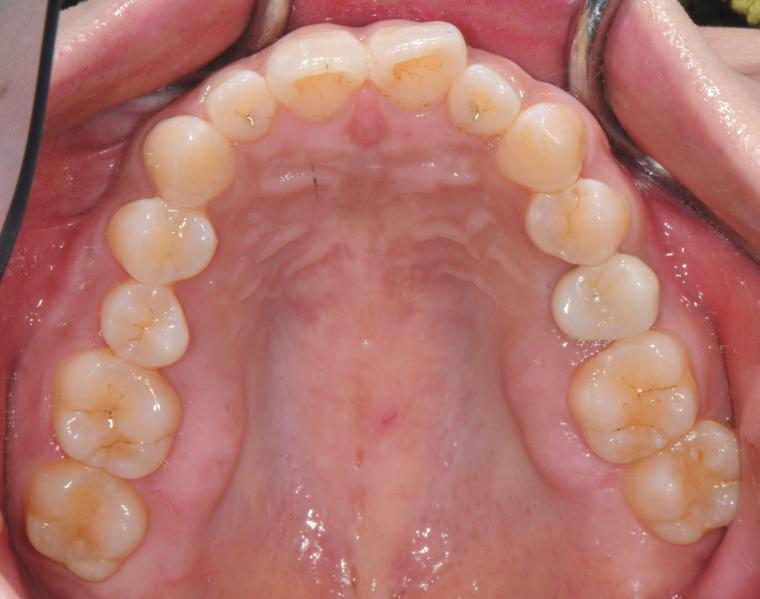

AFTER

33歳女性/上顎1本欠損/インプラント埋込手術

欠損部にインプラントが入り、現在は定期健診で拝見させていただいています。